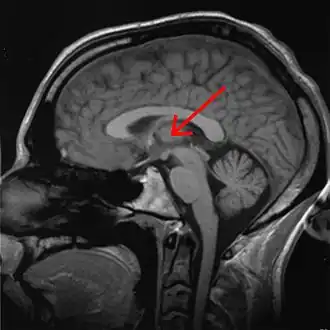

The effects of sleep deprivation on cognitive performance have been studied through the use of parametric visual attention tasks. Functional magnetic resonance imaging of participants' brains who were involved in ball-tracking tasks of various difficulty levels were obtained. These images were taken during rested wakefulness and again after one night of sleep deprivation. The thalamus is more highly activated when accompanied by sleep deprivation—than when the subject is in a state of rested wakefulness. Contrarily, the thalamus is more highly activated during difficult tasks accompanied by rested wakefulness, but not during a state of sleep deprivation. Researchers propose that the thalamic resources, which are normally activated during difficult tasks, are being activated in an attempt to maintain alertness during states of sleep deprivation. An increase in thalamic activation is related to a decrease in the parietal, prefrontal and cingulate cortex activation, resulting in the overall impairment of attentional networks, which are necessary for visuospatial attention performance.[12]

PET scans shows global decrease in glucose metabolism in response to sleep deprivation. As subjects become increasingly impaired on working memory tasks, a more specific decrease of glucose occurs in the thalamus, prefrontal cortex and posterior parietal cortex.[42]

fMRI scans following brief sleep deprivation (24 hours or less) show increases in thalamic activation. Verbal working memory tasks normally cause increases in left temporal lobe activity. After 35 hours come noted decreases in temporal lobe activation and increases in parietal lobe activation.[42]